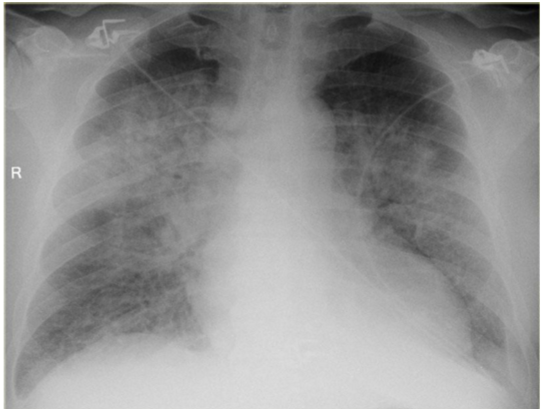

whats the dx for these pics?

Left: normal

Right: pneumonia

pneumonia has ________ opacity

It is (localized/general)

pneumonia

heterogenous

localized